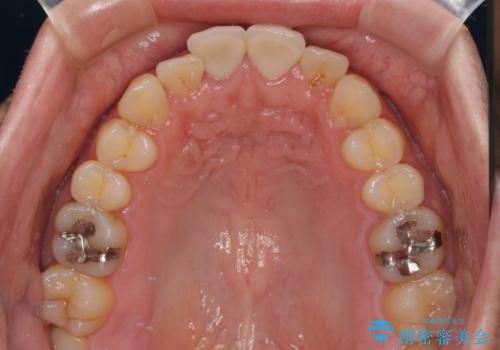

失活した歯は、根管治療を行った後に部分矯正により歯根を引っ張り出し、歯周外科処置により左右の歯肉の位置が揃えることとしました。

強い衝撃を受けた歯であるため、定期的にレントゲン撮影を行い、歯根吸収が起きていたり、神経が失活していたりしないか確認を行い、ある程度安定したところでオールセラミッククラウンにて補綴治療を行うこととしました。

歯をぶつけてから1年後のレントゲン写真を取りましたが、どちらの歯も大きな異常は認められませんでした。

今後も定期的にレントゲン写真による経過観察が必要となります。